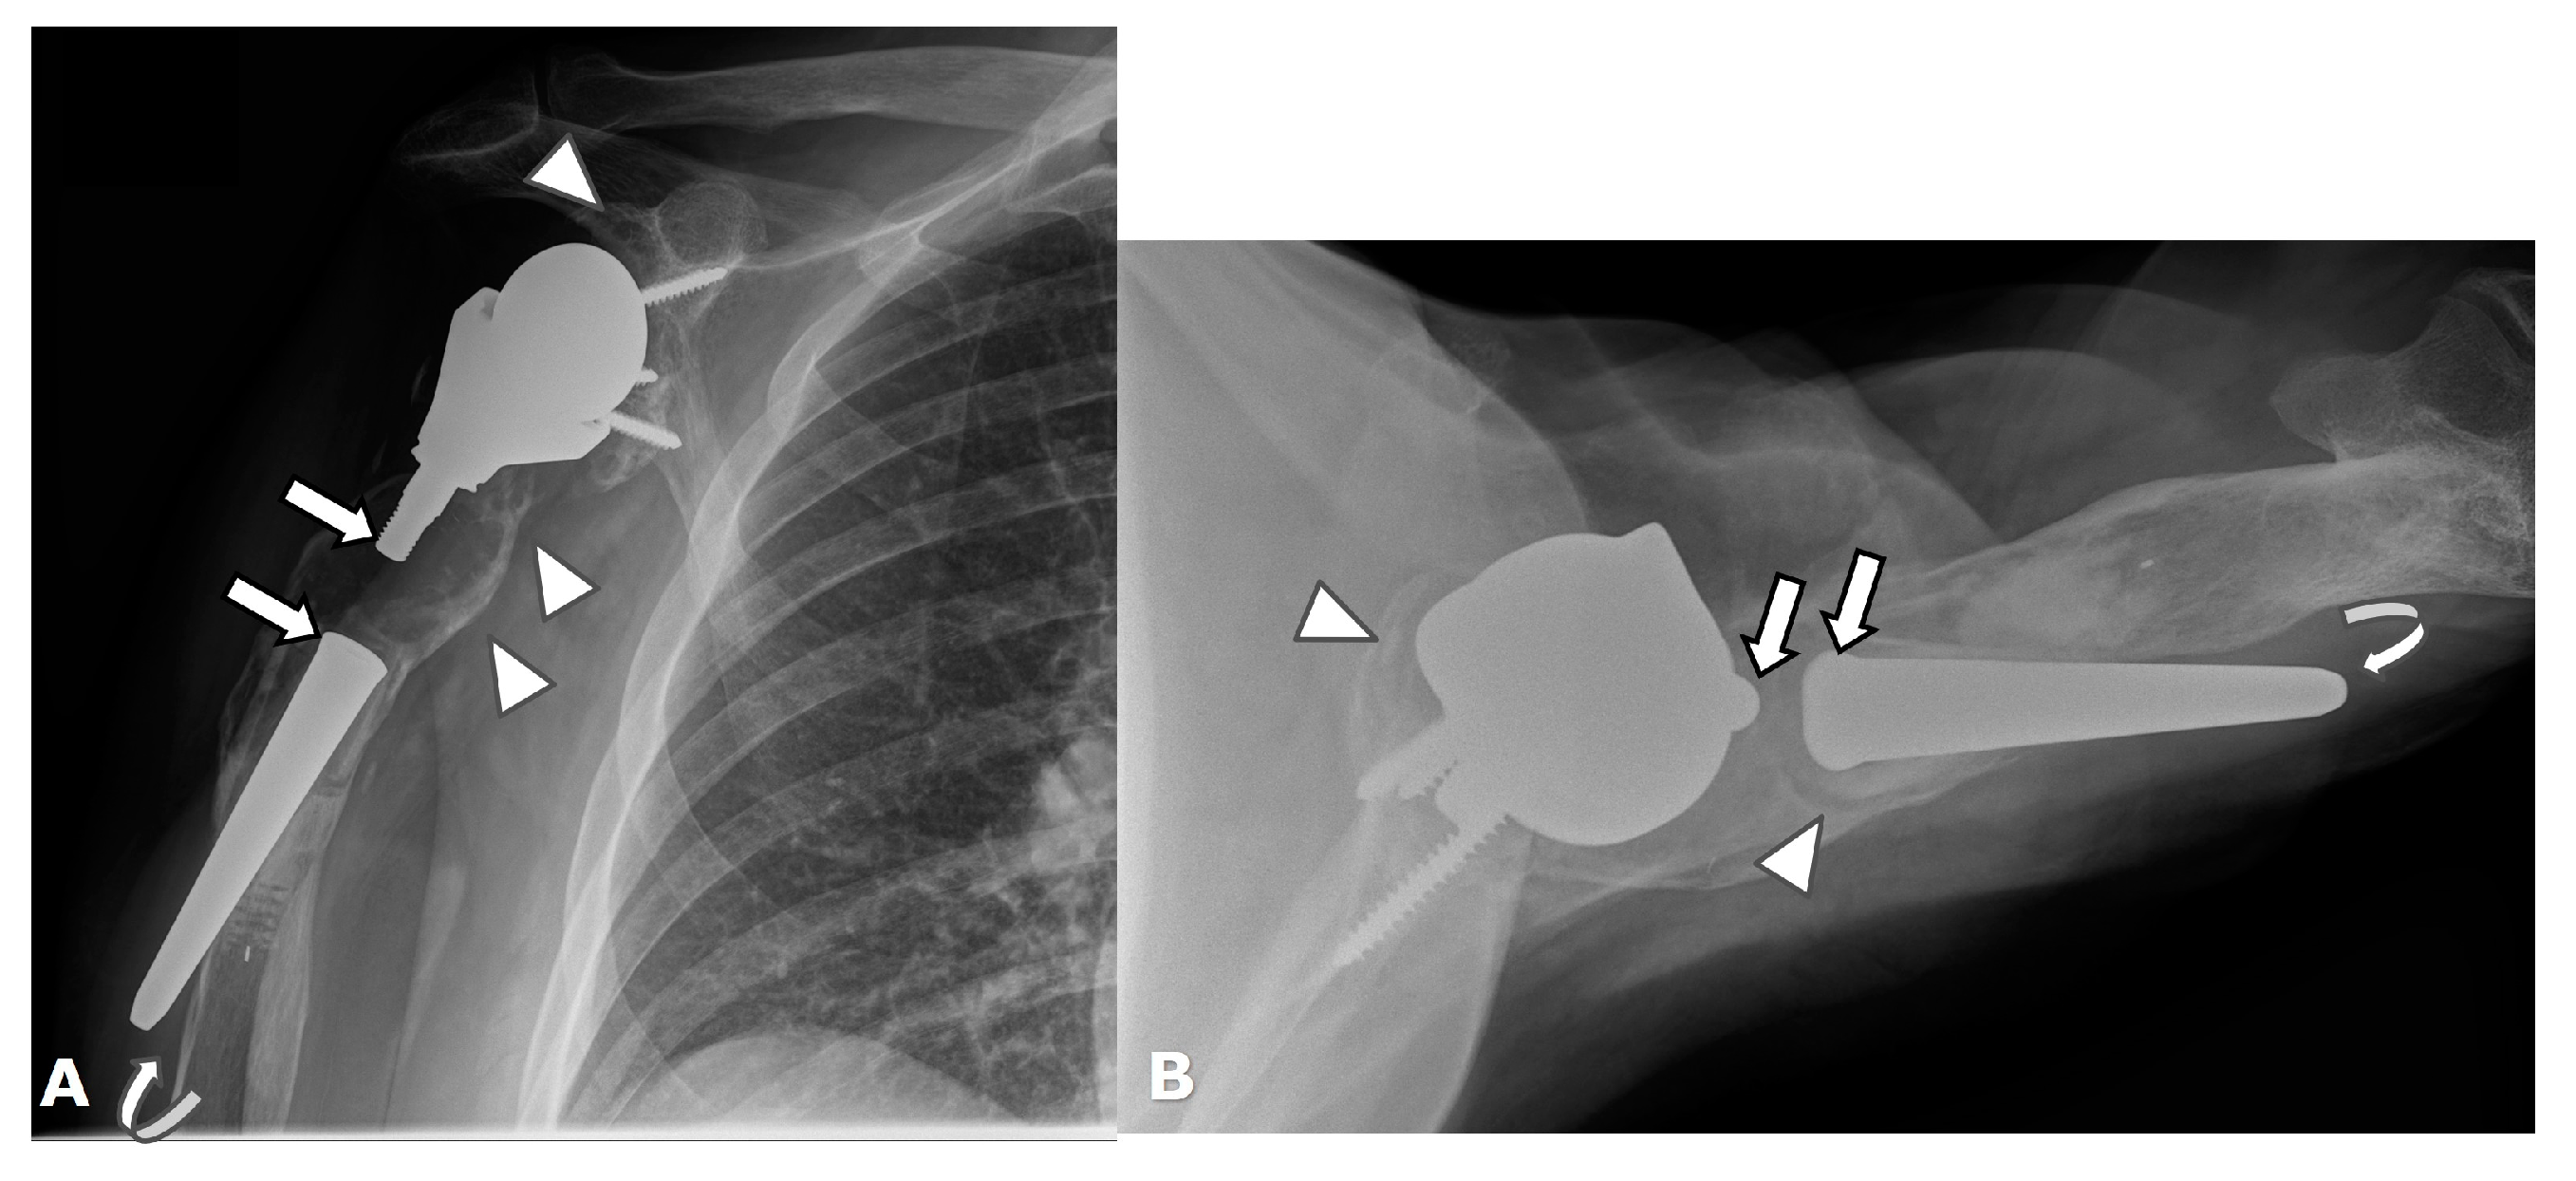

5.3. Revision Shoulder Arthroplasty